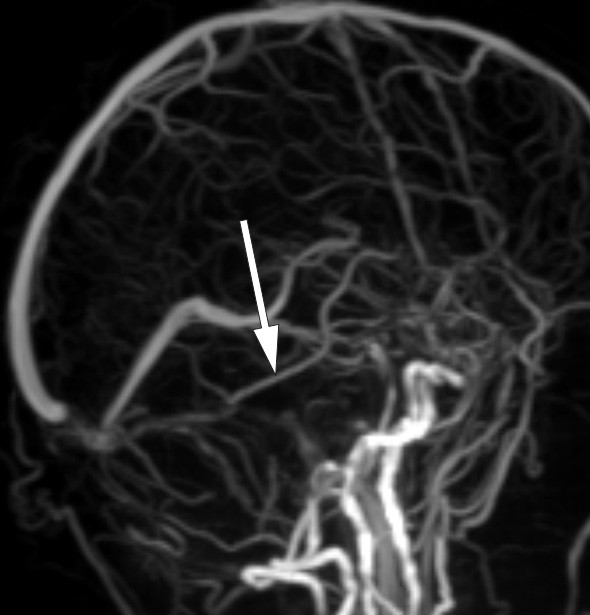

Cerebral CT-undersøkelse viste intet sikkert, men det ble stilt spørsmål om det kunne være noe patologisk i intrakraniale vener. T1-vektet MR-bilde av bakre skallegrop etter kontrastinjeksjon viste trombe i høyre sinus transversus (fig 1), mens venstre side var åpen.

Et mindre antall tilfeller som er blitt studert anatomisk og med CT- eller MR-undersøkelse, indikerer at prosopagnosi som oftest er assosiert med bilaterale lesjoner av mediale oksipitotemporale regioner. Det er rapportert unntak som skyldes unilateral skade, nesten alltid på høyre side (14). Hos vår pasient forelå det en trombe i sinus transversus på nettopp høyre side (fig 1). Venøs drenasje fra temporallappen skjer til sinus transversus via vena Labbé (vena anastomotica inferior), og stase i denne venen kan gi sirkulasjonsforstyrrelse i aktuelle hjerneområde. På MR-bildene var det ingen holdepunkter for diffusjonsavvik eller andre parenkymforandringer. Imidlertid lot ikke vena Labbé seg fremstille på aktuelle side, mens det var godt signal i kontralateral vene (fig 3). I sum anser vi at en sammenheng mellom MR-funn og pasientens kognitive symptomer er sannsynlig.